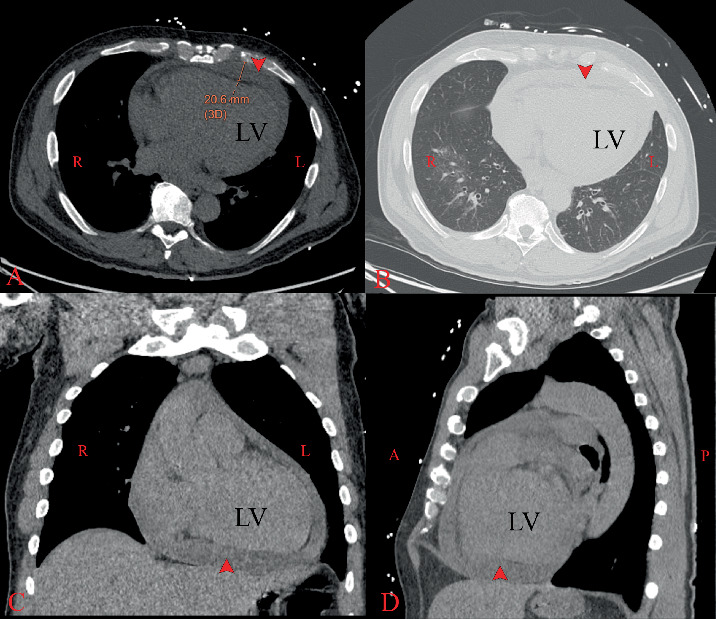

背景:化脓性心包炎是一种罕见的危及生命的疾病,由于抗生素的广泛使用而变得非常罕见。然而,免疫功能低下的患者仍然容易受到这种机会性感染。它通常是由二次细菌源的直接延伸或血液传播引起的。病例描述:我们报告一名55岁男性HIV心肌病患者,因胸痛和呼吸困难从室外转院,心电图提示st段抬高型心肌梗死,提示紧急心导管检查,结果显示冠状动脉正常。床边超声心动图显示大量心包积液伴心包填塞生理征,导致心包穿刺。心包液分析显示白细胞计数高,乳酸脱氢酶水平显著升高,培养肺炎链球菌阳性。尽管接受了抗生素治疗,积液仍重新积聚,需要进行剑突下心包冲洗和引流。剑突活检符合急性骨髓炎。患者出院后接受长期抗生素治疗并安排门诊随访。结论:该病例显示了HIV-AIDS的一种不寻常的表现,突出了用填塞治疗肺炎球菌心包的进展,以及尽管抗逆转录病毒治疗仍存在机会性感染的风险。虽然很罕见,但心包积血可能是致命的;因此,及时诊断和多学科管理对改善预后至关重要。

Background: Purulent pericarditis is a rare, life-threatening condition that has become exceedingly uncommon due to widespread use of antibiotics. However, immunocompromised patients remain susceptible to such opportunistic infections. It is typically caused by direct extension or hematogenous spread from a secondary bacterial source. Case Description: We report a 55-year-old man with HIV cardiomyopathy who was transferred from an outside facility for chest pain and dyspnea, with an electrocardiogram suggestive of an ST-segment elevation myocardial infarction, prompting emergent cardiac catheterization, which revealed normal coronary arteries. A bedside echocardiogram revealed a large pericardial effusion with tamponade physiology, leading to pericardiocentesis. The pericardial fluid analysis revealed a high white blood cell count and a significantly elevated lactate dehydrogenase level, and cultures were positive for Streptococcus pneumoniae. Despite receiving antibiotics, the effusion reaccumulated, necessitating a subxiphoid pericardial wash and drainage. The xiphoid biopsy was consistent with acute osteomyelitis. The patient was discharged with long-term antibiotics and scheduled outpatient follow-ups. Conclusion: This case illustrates an unusual presentation of HIV-AIDS, highlighting advancements in managing pneumococcal pyopericardium with tamponade and the ongoing risk of opportunistic infections despite antiretroviral treatment. Though rare, pyopericardium can be fatal; so prompt diagnosis and multidisciplinary management are essential to improve outcomes.